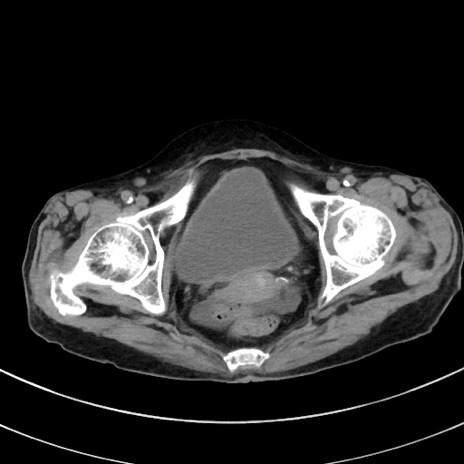

症例33(横断像)

【症例】70歳代 女性

【主訴】心窩部痛

【現病歴】延髄病変の精査・加療にて神経内科入院中。本日より心窩部痛あり。

【身体所見】右下腹部を中心に圧痛と反跳痛あり。

【データ】WBC 10900、CRP 0.02